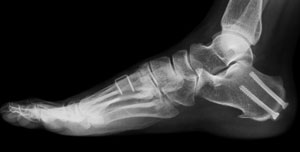

- Your doctor may also perform radiographic exams such as X-ray’s to get a detailed view of the foot and ankle joint to help plan the surgery.

- Tiny wires, pins, or plates may be used to stabilize the bones and keep them in place.